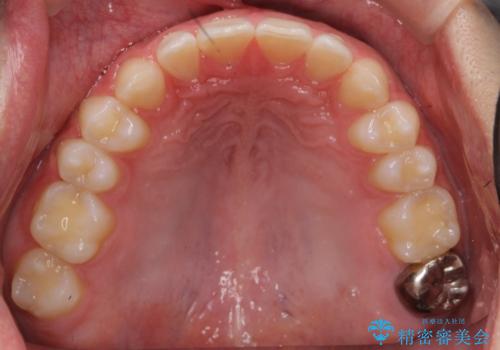

上はインビザラインで目立たないように前歯を下げ、下は難しいため、ワイヤー矯正で咬み込んでいる下の歯を沈める処置を初め行いました。最終的には上下ともインビザライン矯正で仕上げました。

下の前歯が生まれつき1本少なかったため、その部分には最終的にインプラントを入れ、下の歯が下がりすぎないようにかつ上の前歯にしっかり咬むように仕上げました。

今回は、時間はかかりましたが矯正治療で隙間を閉じ、天然の歯を保存することができました。セラミックで無理に一時的にかぶせるとその後大変な人生になるのが予想されます。

難ケースのため、患者様とともに根気強く治療に取り組んだ結果、しっかり治療することができました。